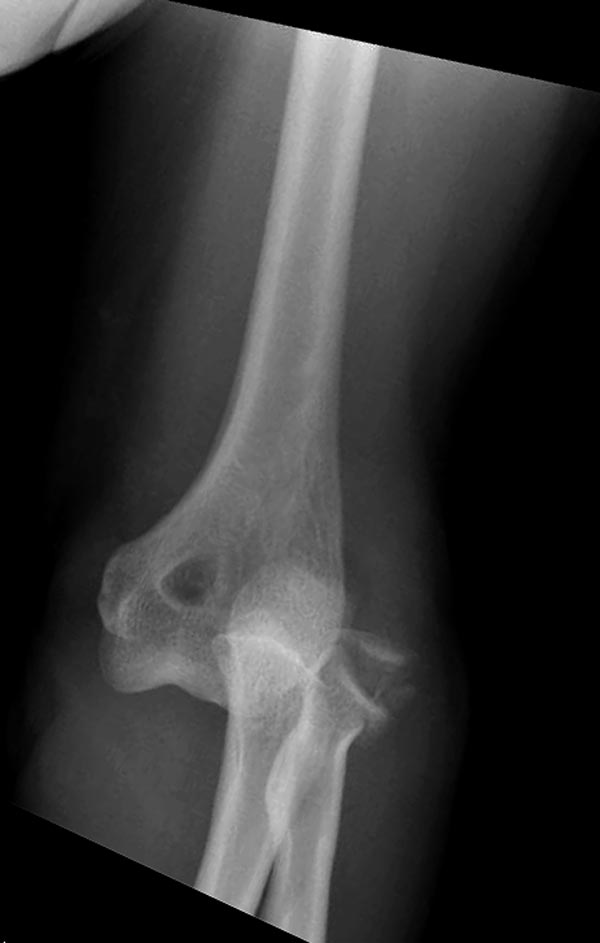

[Ortho] ПЕРЕЛОМ ГОЛОВКИ ЛУЧЕВОЙ КОСТИ.

Второе наблюдение

Вложение не в текстовом формате было извлечено…

Имя     : 3 Elbow radial head fx.JPG

Тип     : image/jpeg